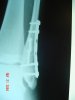

Here's what happened to a buddy last year when he bailed and landed on his foot (came up short on a double). I still remember seeing him fall "out of the sky". :shocked: :crash:

39539_1415671120005_1479410673_30853941_6254917_n.jpg

His boots weren't the greatest and allowed a lot of side bending, he now has new/better boots. :smirk:

View attachment 2741